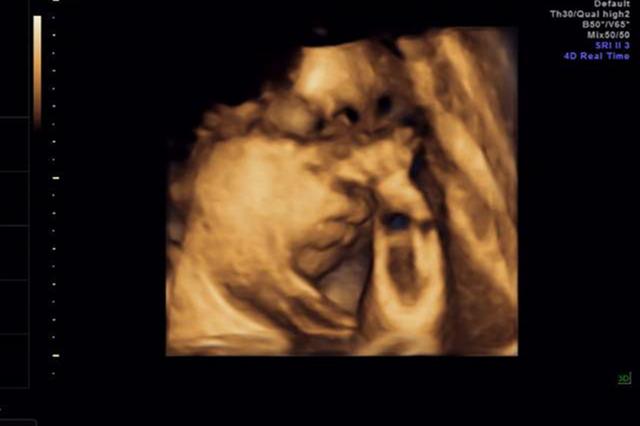

孕期产检8大关,第4关大排畸最难闯,你到哪关了?彩超大排畸 孕期最关键的检查之一:彩超大排畸了。大排畸能检出约80%的胎儿结构异常,比如先天性心脏病。 这关,医生会仔细检查宝宝的五官、手脚、心脏、脊椎等有没有问题,连羊水多少、脐带绕没绕颈都看得清清楚楚。 同时,做完彩超大排畸,妈妈能拿到宝宝的第一张“照片”。 【...

ˇ△ˇ 22张图片揭秘大排畸,看看都查了宝宝哪些结构!大排畸这个词不仅有点陌生,还伴随着一丝隐隐的恐惧。 这究竟是什么检查? 22张切面图到底是看了些什么? 是否真的可以帮我们排除隐患? 今天,我们就跟着一位超声医生的视角,走进一场“大排畸”,看看这22张图片怎么看透一个宝宝的健康密码。 大排畸其实是孕期中一个非常重要的...

胎儿四维超声,最佳检查时间?大排畸,系统超声,三维或者四维超声在具备产前筛查或者产前诊断中心的医疗机构的属于II级超声,II级超声属于胎儿结构筛查B超,III级超声属于产... 充足的羊水和空间可以让胎儿在子宫内活动自如,四维超声检查医生可以更清楚地看到胎儿的各个部位,比如面部、肢体、心脏等结构,从而能够...

“AI+”让超声检查效率翻倍 经过3年临床应用、12.6万例影像数据验证...深圳新闻网2025年3月10日讯(深圳商报记者 张妍)近日,深圳市妇幼保健院红荔院区B超诊室,毕医生正为孕22周的罗静(化名)进行Ⅲ级超声检查。这是整个孕期检查项目最多的一次超声检查,又称为“大排畸”,要针对胎儿的眼球、心血管、四肢、脊柱等多个部位进行扫描,排除颅脑畸形、...